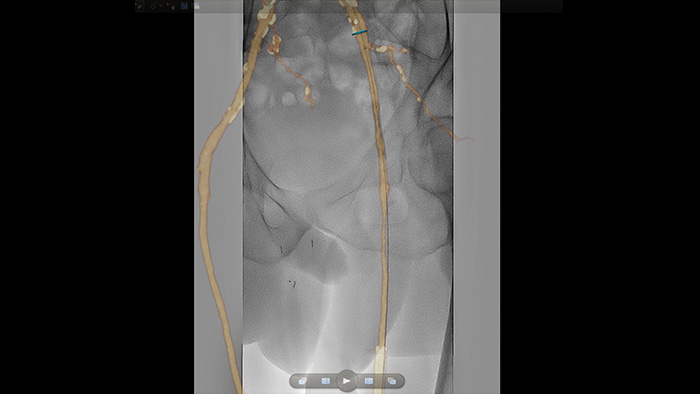

VesselNavigator

VesselNavigator proporciona una hoja de ruta 3D intuitiva y continua basada en conjuntos de datos de CTA y MRA existentes para guiarlo a través de la vasculatura durante los procedimientos periféricos.